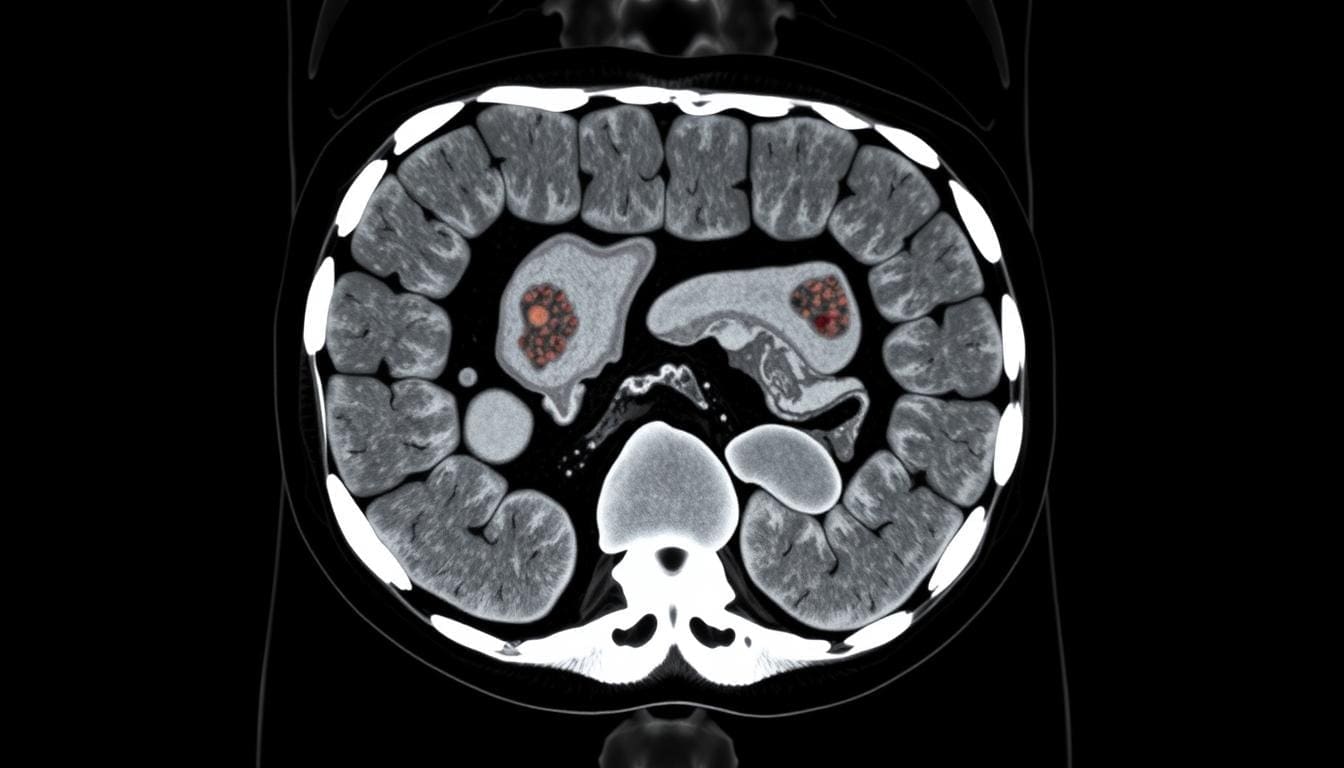

- Computed Tomography (CT) angiography for planning before the procedure and checking after.

Before EVAR, patients get checked to see if they’re a good fit. They have detailed imaging tests like CT scans to measure the aneurysm. We also look at their medical history for any risks.

Ongoing monitoring is key to catch any problems early. This usually means regular imaging like CT scans or ultrasounds. These scans help see how the stent graft is doing and if there are any leaks or other issues.